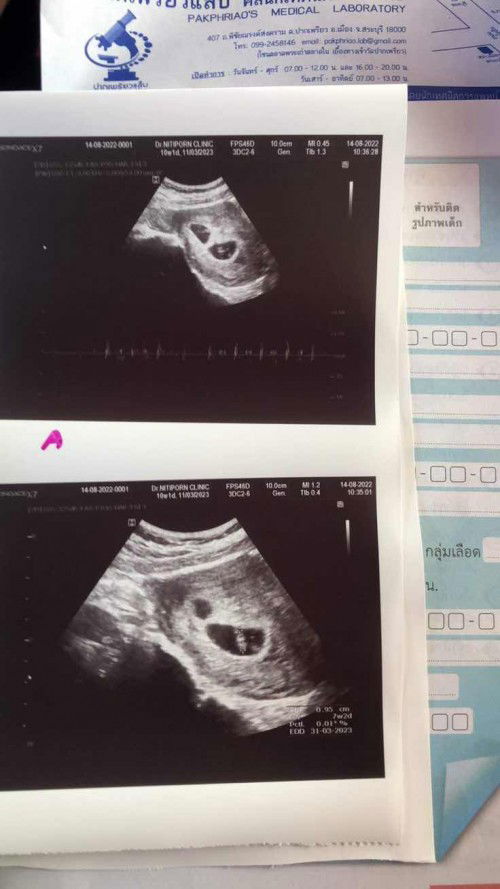

7week1day ซาวเจอ2ถุง หมอบอกว่าแฝด คนนึงเห็นหัวใจ แต่อีกคนไม่เห็น

หมอซาวแล้วพบว่ามีถุงตั้งครรภ์2ถุง ซึ่งน่าจะเป็นแฝด แต่เห็นหัวใจแค่คนเดียว อีกคนมองไม่เห็น หมอจึงส่งตัวไปตรวจที่รพ.อีกครั้งค่ะ หมอบอกว่าตั้งครรภ์เสี่ยงสูง มีแม่ๆท่านไหนท้องแฝด แล้วเจอเหตุการณ์แบบนี้บ้างมั้ยคะ ท้องแฝดเขาว่าเสี่ยงกว่าท้องธรรมดา ครั้งนี้ท้อง2ค่ะ ท้องแรกคนเดียว #ขอบคุณสำหรับคำตอบค่ะ